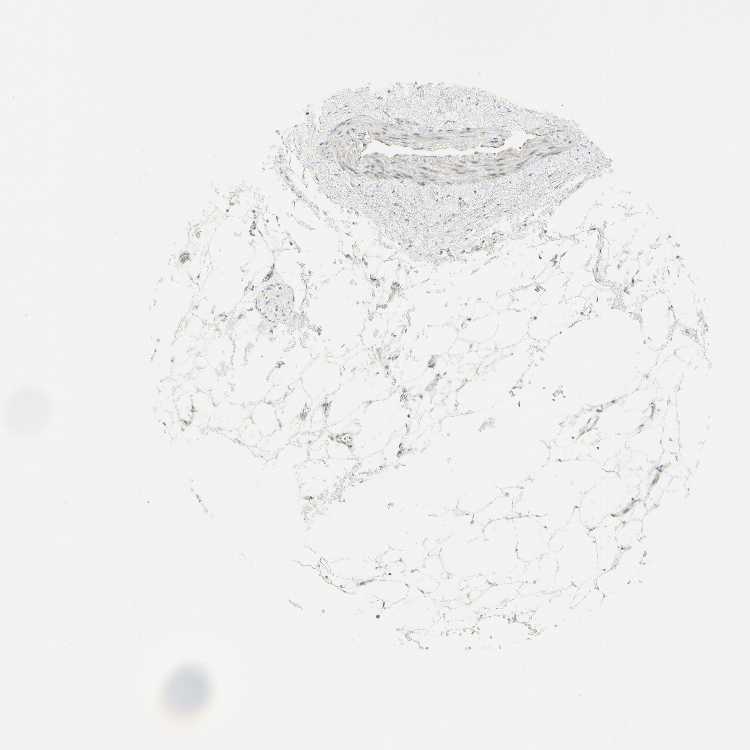

SOFT TISSUE 1 - Antibody stainingi

Antibody staining in the annotated cell types in the current human tissue is reported as not detected, low, medium, or high, based on conventional immunohistochemistry profiling in selected tissues. This score is based on the combination of the staining intensity and fraction of stained cells.

Each image is clickable and will lead to virtual microscopy that enables deeper exploration of all samples and also displays staining intensity scores, fraction scores and subcellular localization as well as patient and tissue information for each sample.

Antibody HPA006916Antibody HPA010568Antibody CAB017617

Chondrocytes -Not detected-

Fibroblasts Not detectedNot detectedMedium

Peripheral nerve Not detectedNot detectedMedium